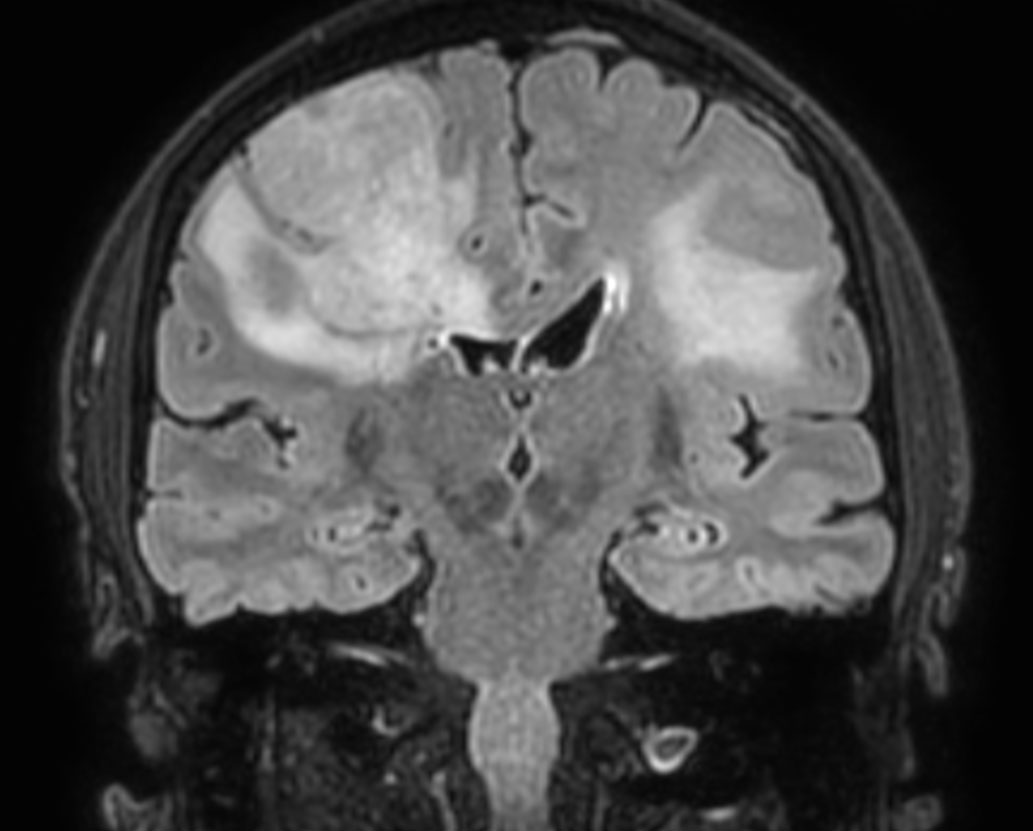

3D BrainVIEW FLAIR (coronal reformat)

3D T1w TFE with gado (coronal reformat)